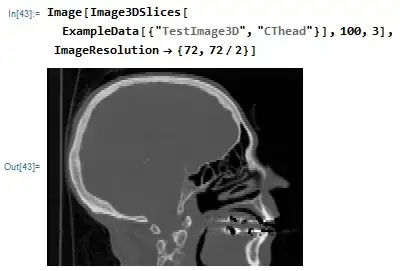

Image[Image3DSlices[ExampleData[{"TestImage3D", "CThead"}], 100, 3],

ImageResolution -> {72, 72/2}]